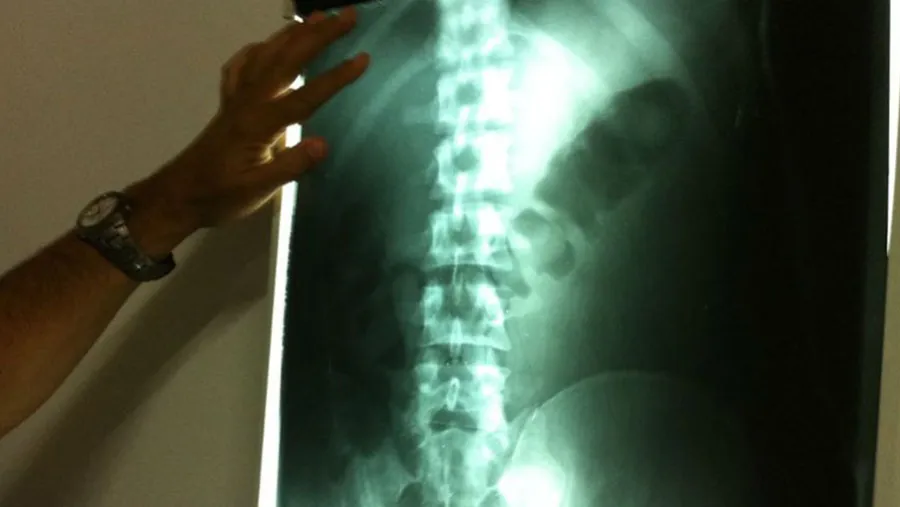

Radiografía que muestra la droga en cápsulas dentro del cuerpo de una mula.

Tan volátil, la noticia se esfumó en el efímero mundo virtual y en esos diarios que solo sirven para envolver huevos. En ese recorrido por Salta, la provincia con la frontera más vulnerable al narcotráfico, este periodista pudo acceder a un material exclusivo donde se ve cómo a un “camello” (se llama así cuando un traficante lleva más cargamento de droga que una “mula”) le sacaron de entre las tripas más de 100 cápsulas de cocaína. Fue operado porque se moría.

Dos días antes de viajar, la mula tiene que suspender la ingestión de sólidos y tomar solo caldo. Entonces se envuelve la cocaína en cápsulas de los dedos de guantes quirúrgicos, con tres capas: dos de guantes y una de papel carbón para despistar rayos X escáneres.

Se atan con hilo dental y se sumergen en miel. Para que las mulas resistan un viaje de doce o quince horas, los traficantes les aplican un medicamento que retarda los movimientos digestivos y que actúa como tranquilizante.

La mujer fue trasladada al hospital de La Quiaca para ser examinada y en las placas radiográficas se detectó la presencia de seis cápsulas alojadas en su estómago. En total fueron 117 cápsulas con un peso de un kilo 290 gramos de cocaína. Intervino el Juzgado Federal de Jujuy”.